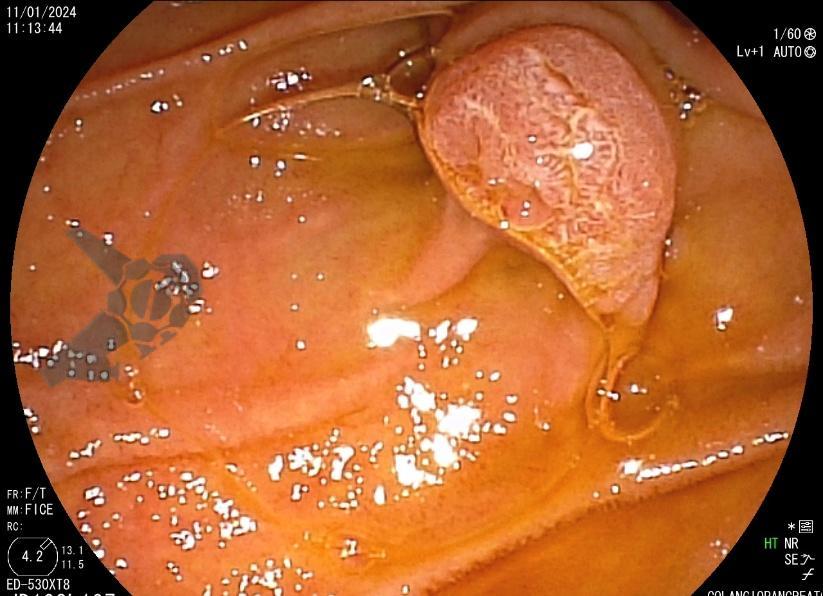

Tendo em vista quadro clínico associado a dilatação de vias biliares, foi indicada colangiopancreatografia endoscópica retrógrada (CPRE) para tratamento de possível estenose da anastomose biliar. Ao se posicionar o duodenoscópio na segunda porção duodenal, identificada lesão polipóide suspeita para adenoma de papila duodenal maior, sendo realizadas biópsias.

Diante da confirmação histológica de adenoma tubular com displasia de baixo grau, optado pelo estadiamento local através de ultrassom endoscópico (EUS), evidenciando lesão restrita a mucosa (sem sinais de acometimento de camada muscular) medindo 12×9 mm, com dilatação de colédoco até 9 mm e ausência de extensão intraductal.